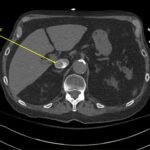

A 78-year-old gentleman presented to the emergency department (ED) for palpitations and dizziness. He had a complicated medical history including atrial fibrillation (AF), recently status post a Watchman procedure, oxygen-dependent chronic obstructive pulmonary disease (COPD), and heart failure with preserved ejection fraction (HFpEF). Point-of-care ultrasound (POCUS) revealed the presence of an intracardiac right atrial thrombus. Computed tomography (CT) angiography confirmed the presence of multiple pulmonary emboli (PE), and extension of the thrombus into the inferior vena cava. Pulmonary emboli are a common complication of thrombus in the right atrium. Management may include anticoagulation, thrombolysis, or thrombectomy. This case highlights that emergency physicians can expedite the diagnosis of intracardiac thrombus by using POCUS. The case presented describes a medically complex patient presenting with symptomatic right intracardiac and inferior vena caval thrombosis complicated by multiple PE. Point-of care ultrasound of the heart and lungs were included in his initial assessment, revealing findings of an intracardiac thrombus, and ruling out multiple other differential diagnoses including pericardial tamponade, pleural effusion, pulmonary edema, and pneumothorax. This finding changed the trajectory of this patient’s evaluation and management, and demonstrates the important role of POCUS in the care of ED patients with undifferentiated cardiopulmonary symptoms.